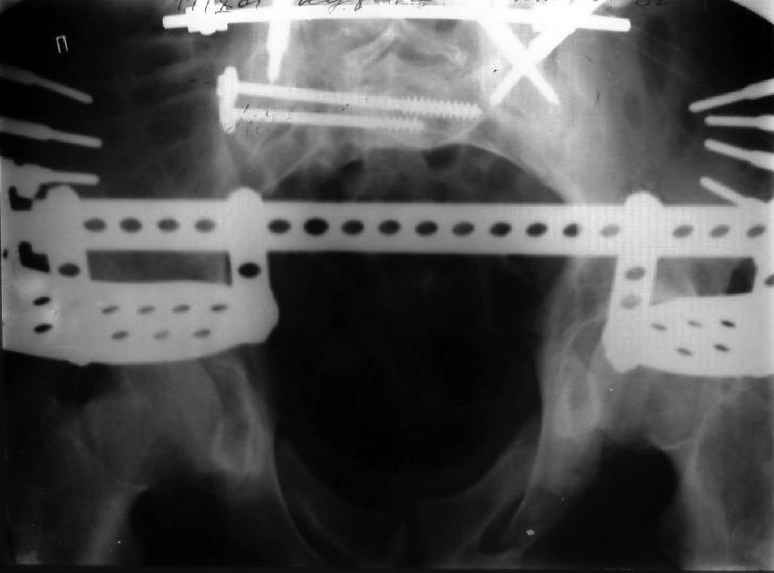

Застарелый перелом таза

Уважаемые коллеги! Хотел-бы обсудить варианты лечения больной с застарелым переломом таза. Возраст 40 лет. Травма 11 месяцев назад. Главный травматолог Камчатского Военно-морского госпиталя Юрий Алексеевич Булахтин

У больного судя по всему вертикальная деформация таза. А каковы основные жалобы пациента и какие у него функциональные требования?

Для принятия решения об оперативном лечении и о его объеме, представляется целесообразным выполнение рентгенографии в проекции "inlet", а так же функциональных рентгенограмм стоя попеременно на правой и левой нижних конечностях (для определения нестабильности тазового кольца).

Мы, как правило, в подобных случаях проводим оперативное лечение в несколько этапов. Первым устраняем деформацию при помощи АВФ (кольцевой конструкции с фиксацией задних отделов), вторым- выполняем введение илиосакралых винтов, накостный остеосинтез передних отделов.

Для информации к размышлению о возможности исправления имеющейся деформации предлагаю похожий случай.